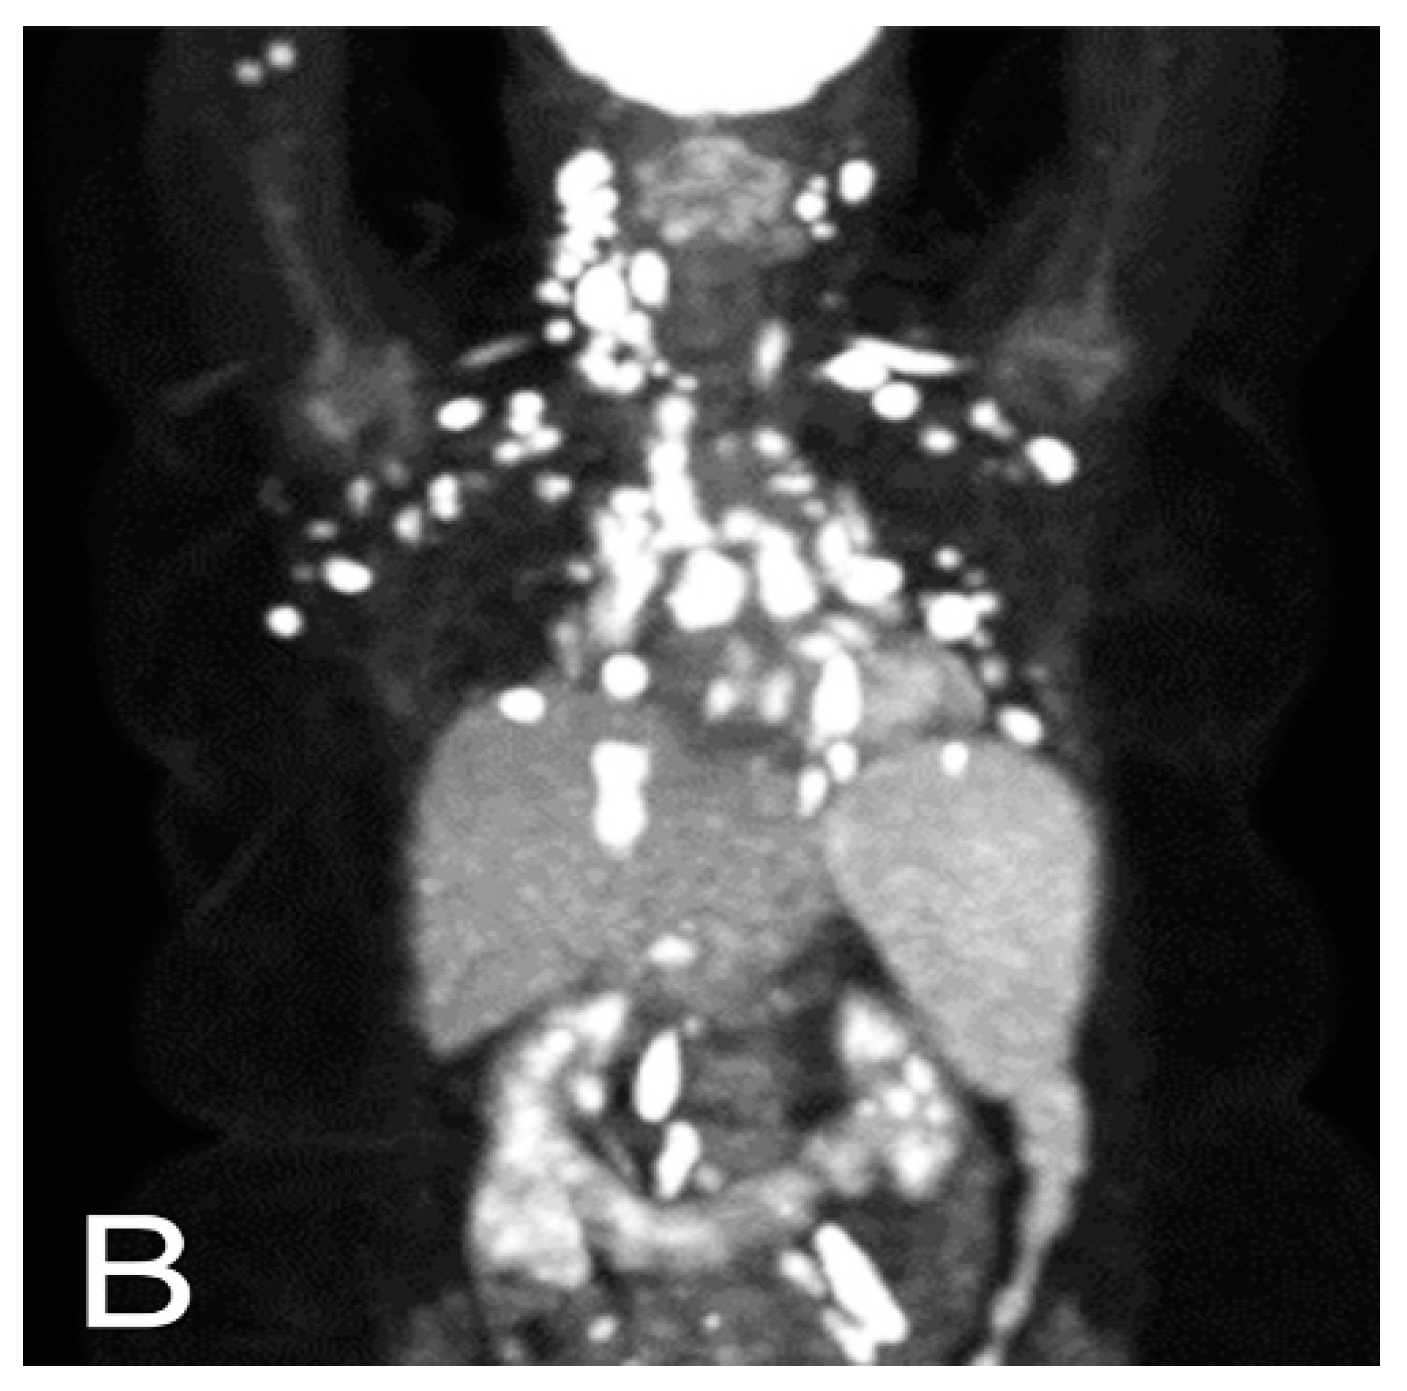

5.1. Computed Tomography (CT)

6. Radiological Differential Diagnosis